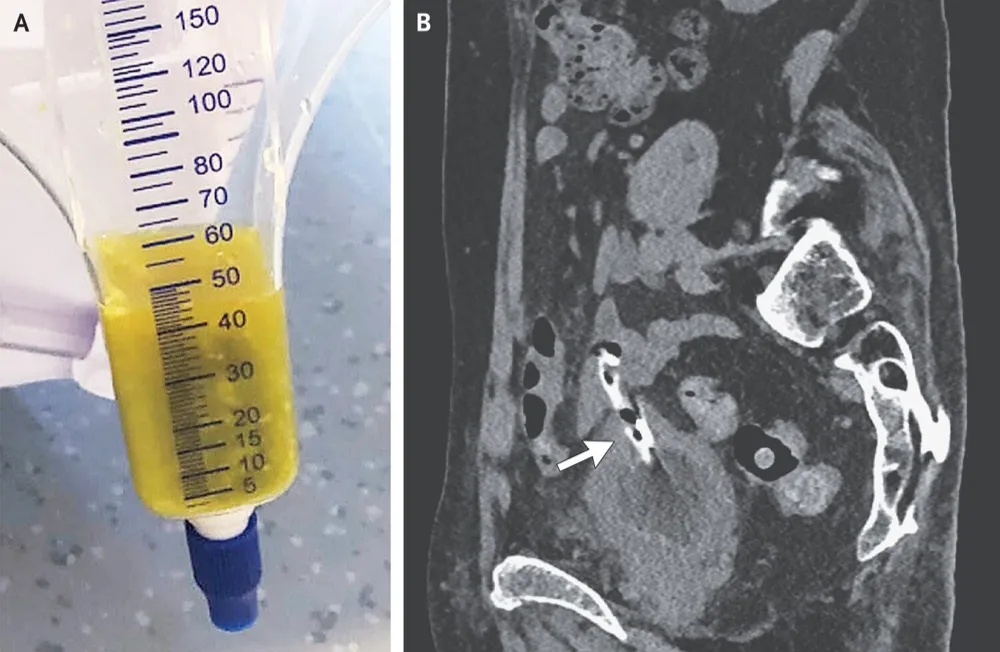

IRA + Icterícia: Um Caso que Exige Investigação Detalhada

IRA + Icterícia: Um Caso que Exige Investigação Detalhada